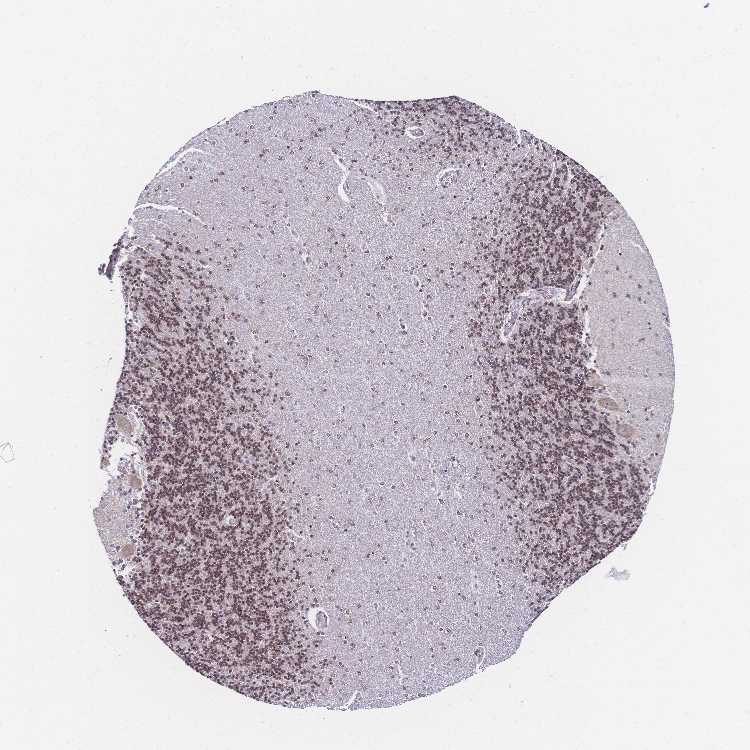

BRAIN CEREBELLUM Show tissue menu

CEREBELLUM - Expression summary

CEREBELLUM - Antibody stainingi

Antibody staining in the annotated cell types in the current human tissue is reported as not detected, low, medium, or high, based on conventional immunohistochemistry profiling in selected tissues. This score is based on the combination of the staining intensity and fraction of stained cells.

Each image is clickable and will lead to virtual microscopy that enables deeper exploration of all samples and also displays staining intensity scores, fraction scores and subcellular localization as well as patient and tissue information for each sample.

Antibody HPA048677Antibody HPA056480Antibody CAB011574

Purkinje cells LowMediumMedium

Cells in granular layer MediumMediumHigh

Cells in molecular layer MediumLowHigh